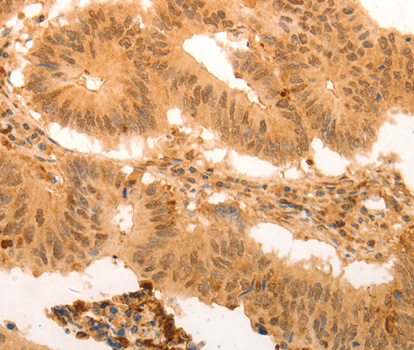

Immunohistochemistry of paraffin-embedded Human colon cancer tissue using SUMO4 Antibody at dilution 1/100.